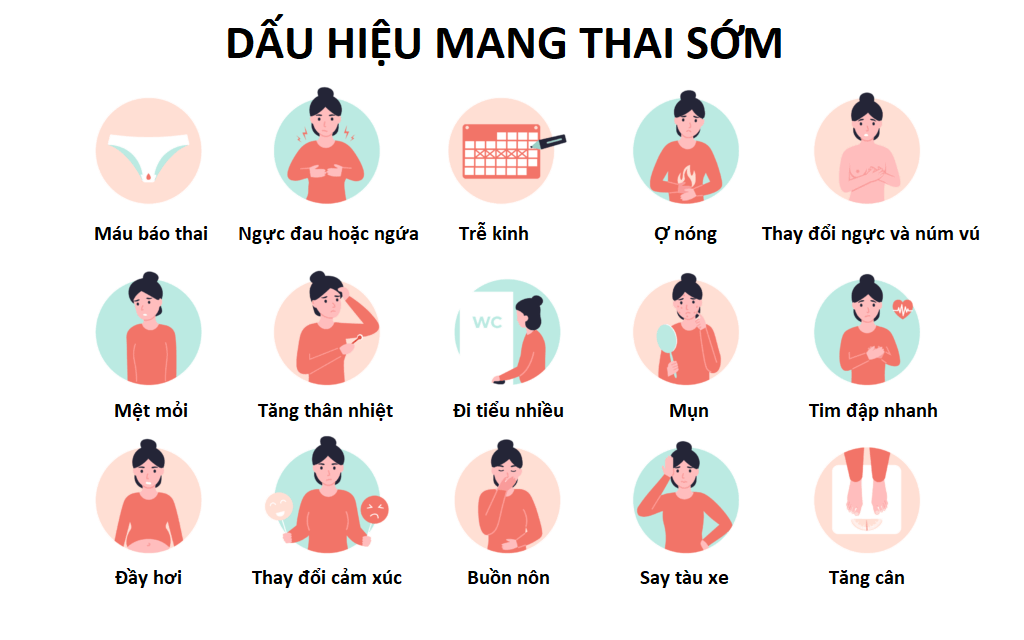

Chào bạn thân mến, Chị hiểu rằng cảm giác chờ đợi, lo lắng khi chu kỳ kinh nguyệt “đến muộn” có thể khiến bạn bồn chồn lắm. Đặc biệt là khi bạn đang mong con, hoặc ngược lại, đang lo lắng về một thai kỳ ngoài ý muốn. Câu hỏi “trễ kinh mấy ngày thì […]

Chắc hẳn đã đôi lần chúng mình trải qua cảm giác lo lắng khi chu kỳ kinh nguyệt bỗng dưng “đình công” mà lại còn kèm theo những cơn đau bụng âm ỉ khó chịu, phải không nào? Tình trạng trễ kinh đau bụng âm ỉ không chỉ là nỗi bận tâm của riêng ai […]

Chào bạn yêu, Chuyenseg biết rằng cảm giác chờ đợi hay lo lắng khi chu kỳ kinh nguyệt bỗng dưng “vắng mặt” thật không hề dễ chịu chút nào. Câu hỏi “trễ kinh bao lâu thì đi khám thai được” chắc hẳn đang quay cuồng trong tâm trí bạn, đặc biệt là khi bạn đang […]

Chào bạn yêu dấu của Chuyenseg, bạn đang lo lắng về việc trễ kinh 3 ngày có sao không phải không? Dù bạn đang hồi hộp mong chờ một tin vui, hay chỉ đơn giản là thấy băn khoăn vì chu kỳ không như thường lệ, chị hiểu cảm giác đó. Đừng lo lắng quá […]